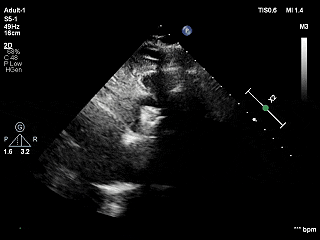

TEER手术过程

建立右侧股静脉入路,在食道超声引导下进行房间隔穿刺,获得穿刺高度4.1cm,交换Super Stiff超硬导丝至左上肺静脉,使用血管鞘扩张股静脉后,沿超硬导丝送入可操控导引导管(SGC)至左房,将第一枚二尖瓣夹输送系统(CDS-XTR)送入左心房。送入夹子过程中为避免碰到左房组织完成Straddle“骑跨”,顺利完成Straddle并将夹子打弯至二尖瓣环水平。接下来为避免发生缠绕在1区进行轨迹测试,使夹子的运动轨迹指向心尖。在心房侧打开夹臂,调整夹臂方向指向12点-6点方位,与二尖瓣对合缘垂直。完成调整后将夹子移动至3区位置,将二尖瓣夹关紧后缓慢送入左心室。在左室打开夹子重新确认Orientation。准确成功捕捞3区前叶脱垂及反流区域,确认瓣叶瓣尖稳定插入夹臂后,Gripper Down,观察到明显Bouncing后,关紧夹臂予以夹合,夹子内侧反流消失,夹子外侧还有残余脱垂及中量反流。考虑瓣叶长度11mm以上,瓣口面积足够,决定在外侧Side by Side再植入一枚XTR,植入两枚XTR后活动稳固,反流降至Trace。术后肺静脉逆流消失,二尖瓣平均跨瓣压差2mmHg。

房间隔穿刺高度4.1cm

SGC穿房间隔进入左房

第一枚XTR进入左房

在1区进行轨迹测试和Orientation调整

将调整好的夹子移动至3区下左室

在左室打开夹子确认Orientation

捕捞瓣叶,确定瓣叶瓣尖稳定插入夹臂后,Gripper Down

Gripper Down后Bouncing明显

夹子关紧后,前后叶受限明显

夹子内侧反流消失

夹子外侧残余脱垂与反流

3D Enface下组织桥稳定残余外侧前叶脱垂

3D Enface上彩可见夹子内侧无反流,残余外侧反流

送入第2枚XTR在左房调整轨迹及Orientation

进入瓣下重新确认Orientation及位置

关紧后,前后叶受限明显

3D Enface下组织桥稳定无反流

夹子释放后,反流基本消失

LVOT切面可见主瓣二尖瓣术后反流基本消失

植入两枚夹子后二尖瓣平均跨瓣压差2mmHg